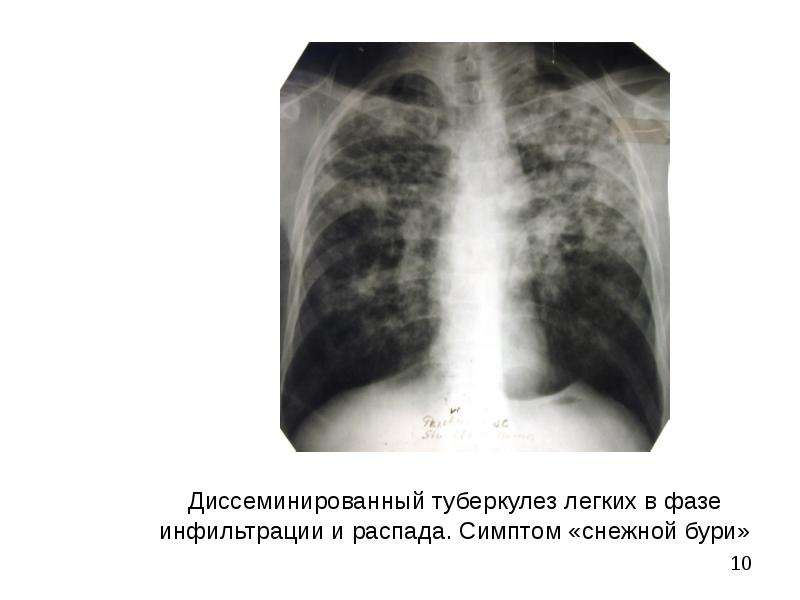

Симптомы и признаки туберкулеза: как распознать заболевание

Раздел: Визуальные уроки